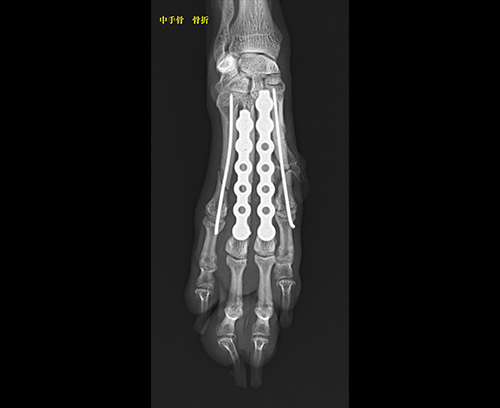

中足骨骨折

中手骨骨折